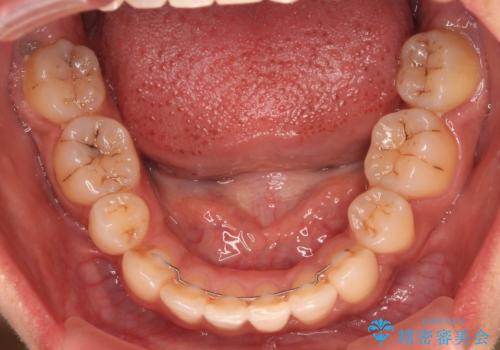

- 八重歯と上下前歯のでこぼこを気にして来院された患者様です。

上下前歯部叢生のスペース獲得のため、上下顎左右小臼歯各1歯(計4本)を抜歯して、ワイヤー装置にて矯正治療を行うこととしました。

上下の正中位置が大きくずれていたため、上下正中が合わないまま終了することが予想されましたが、思っていた以上にスムーズに歯が移動し、満足いただける仕上がりとなりました。